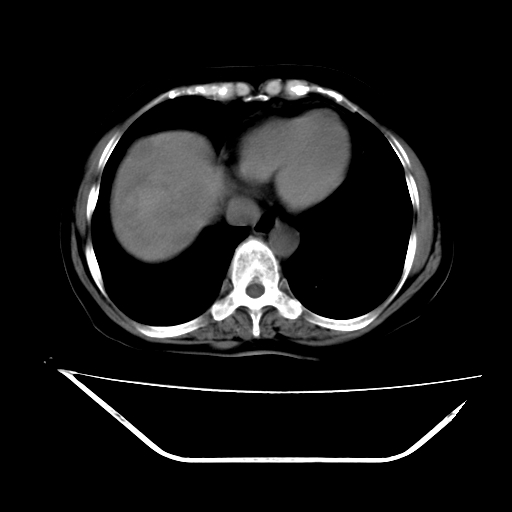

2008-11-10ct平扫(其间去中山医院诊治未行特殊治疗)

2008-11-10ct平扫见并肝内、血膜下血肿基本吸收,肝内低密度灶缩小。此时再做增强ct应有显着意义。对患者/医者都好!

从平扫+增强及治疗后复查片,病变明显缩小,不考虑肝癌出血可能,还是考虑为良性病变可能性大;单纯血肿并包膜下积液吧,病变强化没法解释,肝血管破裂出血吧,增强不符合典型血管瘤的表现,良性肿瘤破裂出血吧,复查片看来好像也不太支持(没做强化也不太好说)。本人还是考虑单纯肝内血肿并包膜下积液,强化是不是血管有外渗。

患者自6月至11月,如果是肝癌,没有经过特殊治疗,想必应该会有所进展吧,而不是ct所见,反而似有病灶减小的趋势。建议增强。